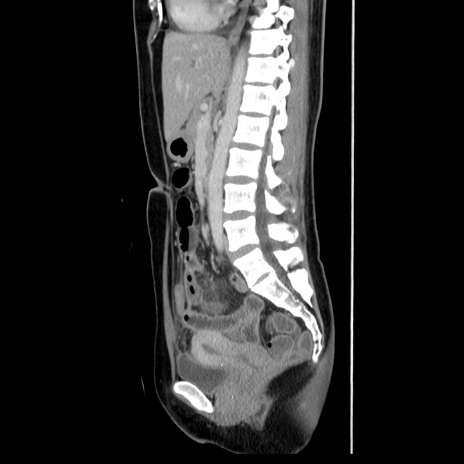

症例39(矢状断像)

【症例】40歳代女性

【主訴】上下腹部痛

【現病歴】2日目から下腹部痛あり。夜間は痛みで眠れなかった。昨日より上腹部痛と下痢が出現。臥位で痛みは軽快したため、休んでいた。本日になって臥位でも立位でも痛みが強くなってきたため救急要請。

【既往歴】子宮内膜症

【身体所見】部:平坦・軟、左上下腹部に圧痛あり、反跳痛あり。

【データ】WBC 21800、CRP 26.78

CT